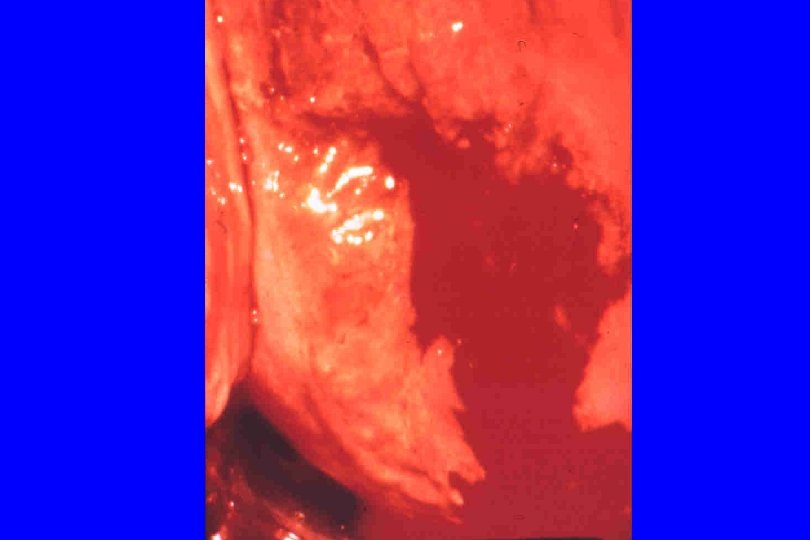

Endocervix Ectocervix

Endocervix Ectocervix

Diagnosis of Cervicitis · · Signs: specific, but insensitive. Include: - easily induced bleeding (“friability”) “Endocervicitis” - mucopurulent discharge: swab test - edematous ectopy - discrete lesions (ulcers): can occur anywhere Increased PMN (“polys; ” >10 -30/HPF) on Gram stain of endocervical secretions: may be sensitive for endocervicitis, but not specific; variable in ectocervicitis

The Cervix and Trichomoniasis l Classic: “strawberry cervix” Ø Focal areas of superficial hemorrhage surrounded by paler mucosa Ø May also see more subtle petechiae Ø More common with relatively moderate-severe Trichomonas vaginitis

Cervicitis due to Trichomonas vaginalis